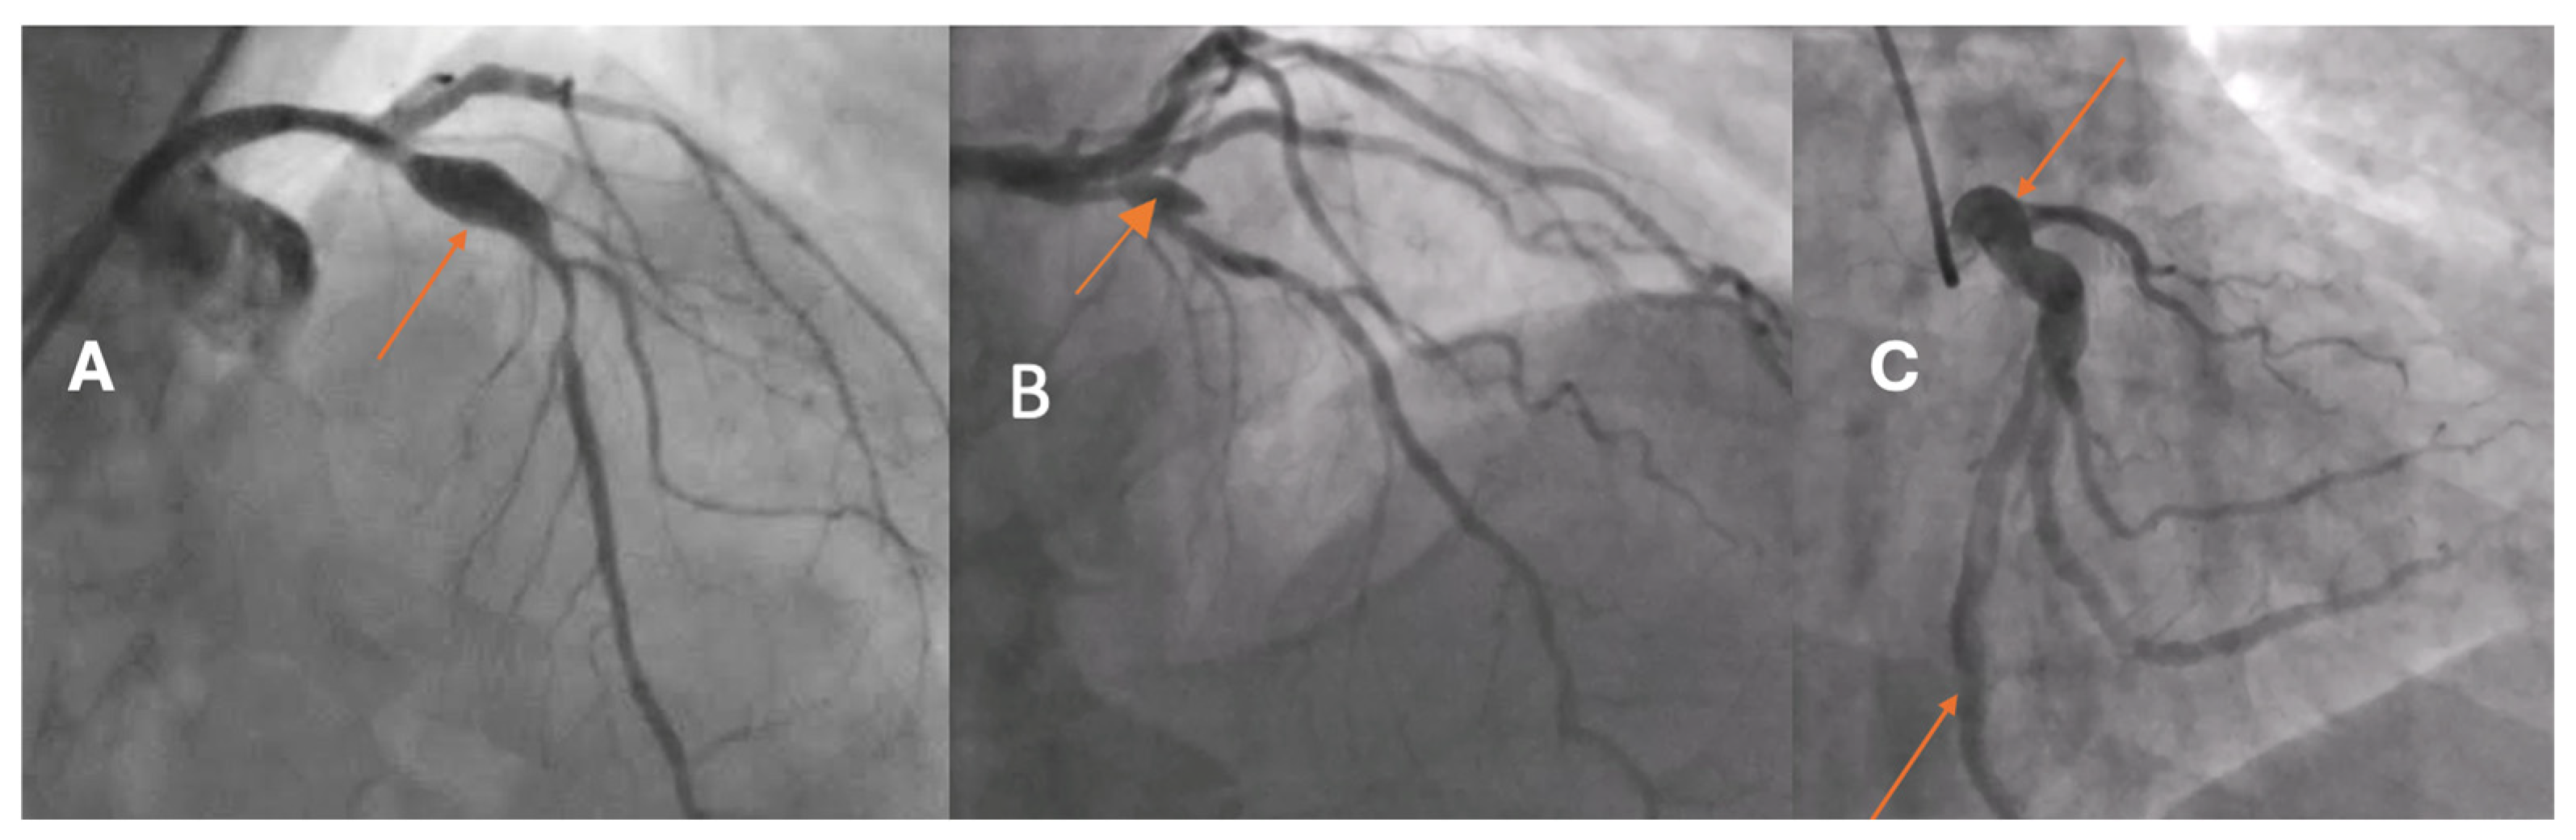

OCT-based analysis of aneurysmal remodeling:

Quantitative analysis was performed using optical coherence tomography (OCT) pullbacks (The OPTIS Next Imaging System by Abbott) obtained during optimal contrast clearing and a stable catheter position (

Figure 2). The aneurysmal segment was defined as the cross-section exhibiting the maximal luminal area within the visibly dilated portion of the vessel. The diameter was determined as the mean lumen and external elastic membrane (EEM) areas of proximal and distal reference cross-sections, located at least 5 mm away from the aneurysmal borders and appearing free or minimally affected by atherosclerosis, in accordance with established intravascular imaging standards [

10,

11]. When one or both adjacent segments were unsuitable due to diffuse disease, the least-diseased portion of the same vessel or the largest angiographically normal coronary artery was used as the reference [

2,

12]. CAA was defined as a focal luminal enlargement ≥1.5 times the reference diameter or >50% greater lumen area, consistent with prior angiographic and intravascular definitions [

13].